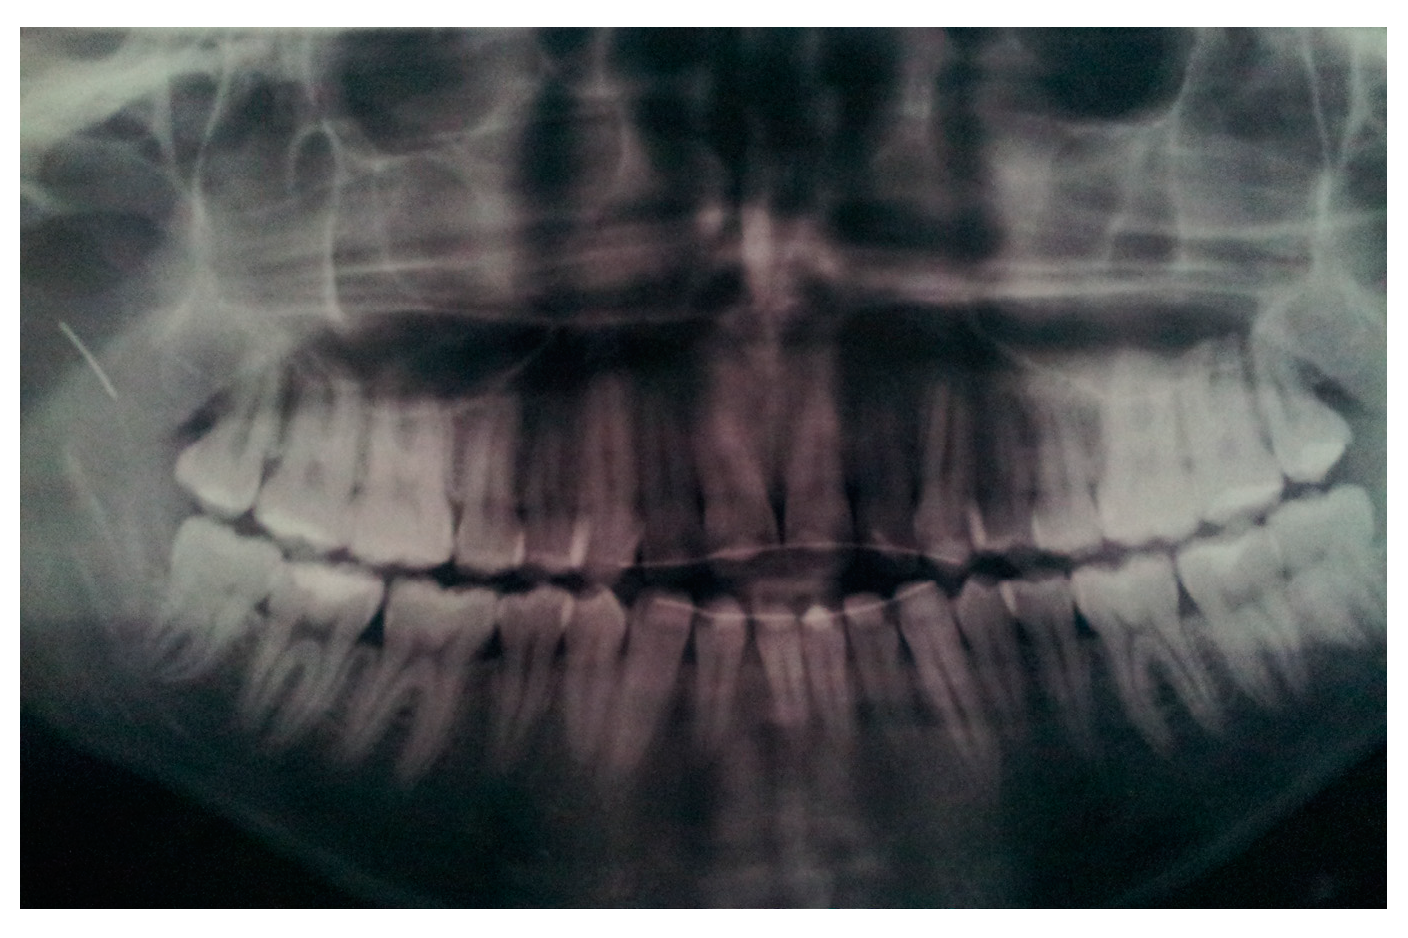

- Dental landmarks: they can be used as an alternative to the occlusal splint. This method requires the presence of at least 4 to 5 non-periodontopathic dental elements in the upper dental arch on which dental brackets could be placed.